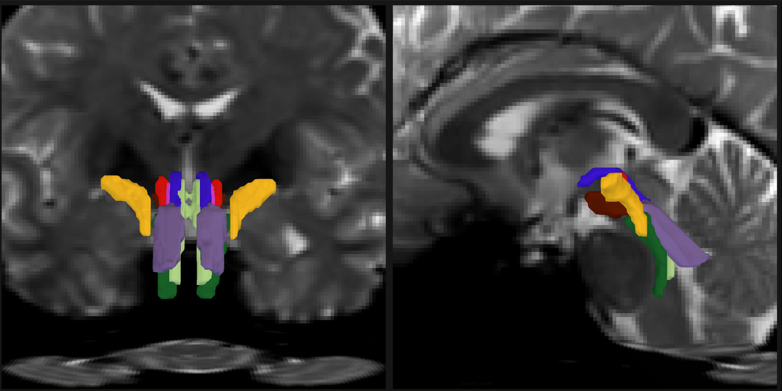

In a new study, a team of MIT, Harvard University, and Massachusetts General Hospital researchers unveil AI-powered software capable of automatically segmenting eight distinct bundles in any diffusion MRI sequence.

As part of his thesis work to better understand the neural mechanisms that underpin consciousness, Olchanyi wanted to develop an AI algorithm to overcome these obstacles. BSBT works by tracing fiber bundles that plunge into the brainstem from neighboring areas higher in the brain, such as the thalamus and the cerebellum, to produce a “probabilistic fiber map.” An artificial intelligence module called a “convolutional neural network” then combines the map with several channels of imaging information from within the brainstem to distinguish eight individual bundles.

To train the neural network to segment the bundles, Olchanyi “showed” it 30 live diffusion MRI scans from volunteers in the Human Connectome Project (HCP). The scans were manually annotated to teach the neural network how to identify the bundles. Then he validated BSBT by testing its output against “ground truth” dissections of post-mortem human brains where the bundles were well delineated via microscopic inspection or very slow but ultra-high-resolution imaging. After training, BSBT became proficient in automatically identifying the eight distinct fiber bundles in new scans.

Olchanyi, Brown and their co-authors applied BSBT to scores of datasets of diffusion MRI scans from patients with Alzheimer’s, Parkinson’s, MS, and traumatic brain injury (TBI). Patients were compared to controls and sometimes to themselves over time. In the scans, the tool measured bundle volume and “fractional anisotropy,” (FA) which tracks how much water is flowing along the myelinated axons versus how much is diffusing in other directions, a proxy for white matter structural integrity.

In each condition, the tool found consistent patterns of changes in the bundles. While only one bundle showed significant decline in Alzheimer’s, in Parkinson’s the tool revealed a reduction in FA in three of the eight bundles. It also revealed volume loss in another bundle in patients between a baseline scan and a two-year follow-up. Patients with MS showed their greatest FA reductions in four bundles and volume loss in three. Meanwhile, TBI patients didn’t show significant volume loss in any bundles, but FA reductions were apparent in the majority of bundles.